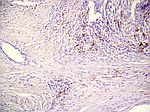

Malignes Melanom, HE